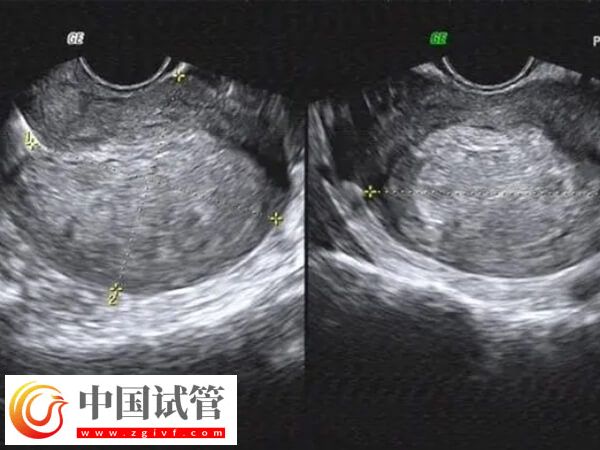

- 检查3次:采用阴道超声或性激素检测结合超声的方式,需要根据患者子宫内膜的生长情况来判断,要检查到子宫内膜厚度约10毫米且容积不小于2毫升时才可进行移植,所以可能需要多次检测,如3次左右;